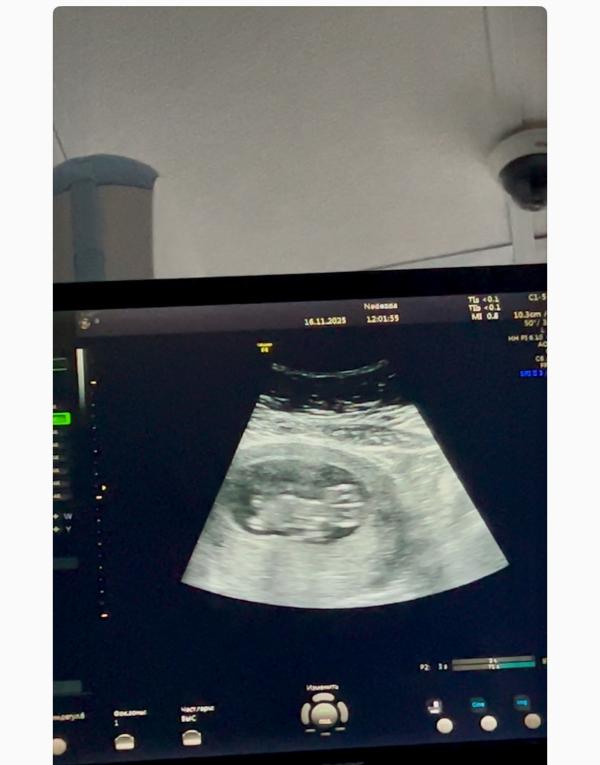

Первое УЗИ при беременности: эмоции и волнение мамы

Ходила сегодня на свидание, махал мне ручками 🥹🥹🥹 прям плавает уже там

Ктр 43,4 по узи уже 11,1 неделя

25 жду скрининг, надеюсь с крошкой все хорошо 🙏🥰